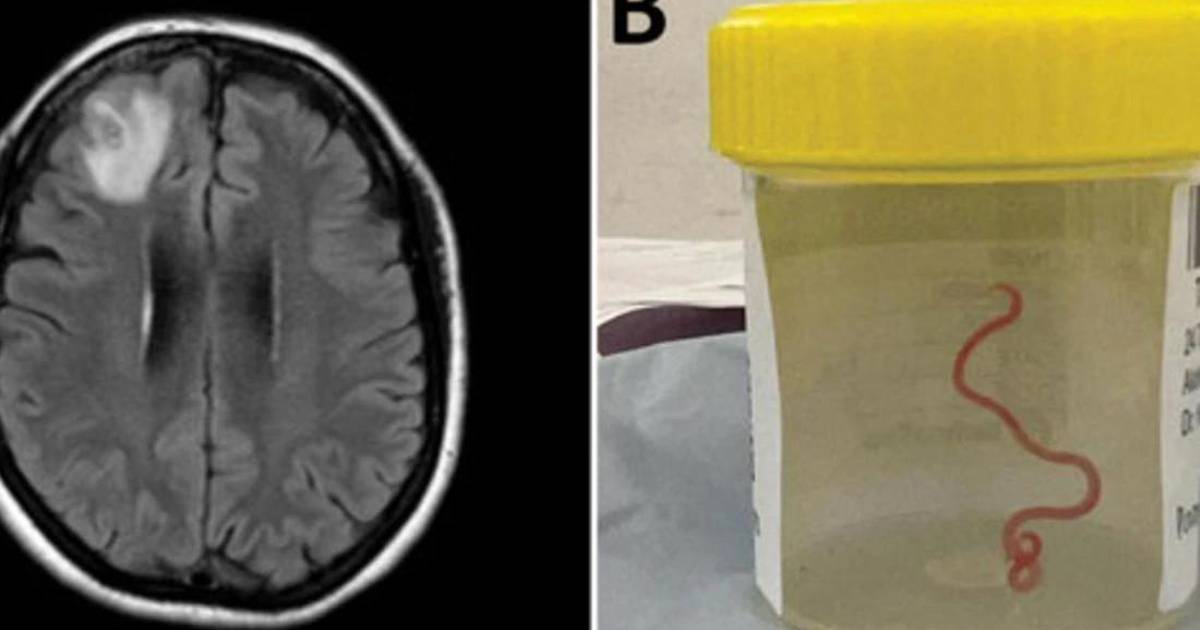

En 2022, la paciente se sometió a una resonancia magnética tras experimentar trastornos en la memoria y depresión. Las imágenes del cerebro de la paciente revelaron que la mujer tenía una lesión atípica en el lóbulo frontal derecho.

Un neurocirujano del Hospital de Canberra exploró la anomalía y fue entonces cuando se encontró la inesperada lombriz intestinal de 8 centímetros.

El parásito fue extraído, vivo y retorciéndose, de la paciente durante una cirugía cerebral, de la que no se precisa la fecha, y actualmente la mujer continúa siendo examinada por el equipo de especialistas en enfermedades infecciosas y cerebro.